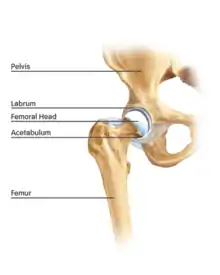

Figure 1. Basic anatomy of the hip joint

The hip is essentially a ball and socket joint. It consists of the head of the femur (the ball) and the acetabulum (the socket). Both the ball and socket are congruous and covered with hyaline (or articular) cartilage, which allows smooth, almost frictionless gliding between the two surfaces. The edge of the acetabulum is surrounded by the acetabular labrum, a fibrous structure that envelops the femoral head. (See fig. 1) The labrum acts as a seal, or gasket, around the femoral head. However, this is not its only function, as it has been shown to contain nerve endings, which may cause pain if damaged.[18] The blood supply of the labrum has also been demonstrated.[25] The joint itself is encompassed by a thick, fibrous joint capsule, which is lined by synovium. The ligaments that keep the hip joint in place are in fact, thickened areas of joint capsule, rather than distinct structures. The synovium generates fluid that lubricates the joint; in that fluid are the nutrients needed to keep the cartilage cells alive. A total of 27 muscles cross the hip joint, making it a very deep part of the body for arthroscopic access. This is one reason why hip arthroscopy can be quite technically demanding.

The cartilage lining of the socket is in the shape of an inverted horseshoe. The middle of this is termed the cotyloid fossa. Arising from the cotyloid fossa and connecting to the femoral head lies the ligamentum teres. The function of this in the adult is under debate, but in childhood the ligamentum teres carries a blood vessel from the pelvis to the femoral head. This blood vessel usually becomes redundant with age. Arthroscopic hip surgeons are becoming increasingly convinced that the ligamentum teres acts as an internal stabiliser of the hip joint, and pathological injury to the ligament is now a recognised cause of hip pain and instability.[8][26]